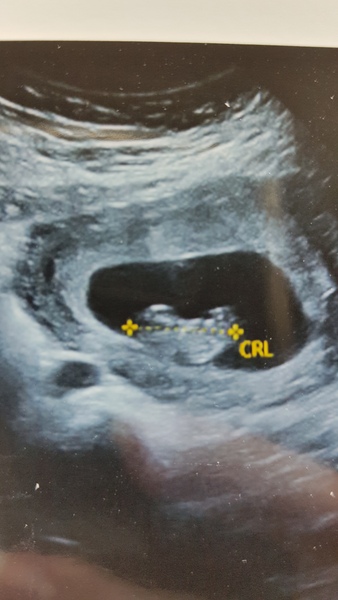

Hi folks, hope you're all well. I thought I would share my early scan photo from yesterday... I had the early scan simply because I am impatient and it was really cheap. I also just wanted to check I was pregnant, because like others, I sometimes have days where I forget I'm pregnant or doubt whether I am.

I can confidently say I have a little human with a strong (173bpm) heartbeat growing inside me and I am so ecstatic (hearing the heartbeat did bring a tear to my eye)!! It has made it very real and I am actually 5 days further along than previously thought. So now I'm 9 weeks 5 days and yet to have my booking in appointment (got it tomorrow). Hopefully won't be too late for a 12 week scan/tests.